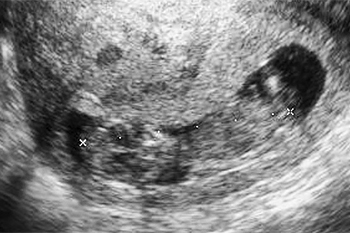

妊娠14週

子宮を横方向に撮影 9週0日

下から縦方向に撮影 9週0日

胎内での窮屈な姿勢は、生まれてからの向きぐせや体のゆがみ、コリにつながりやすくなります。また、膝が伸びた状態が妊娠後期まで続くと、股関節脱臼になりやすいという研究発表もあります。